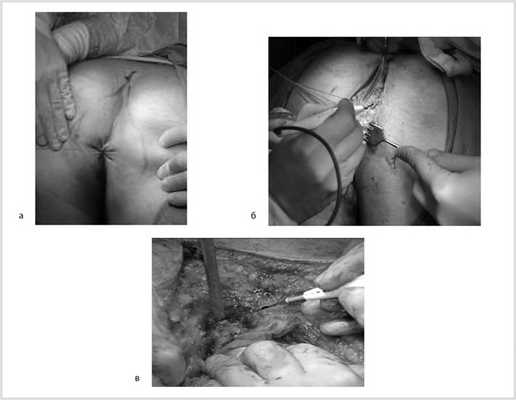

Гистологическое заключение: в жировой клетчатке прямой кишки, с учетом иммуногистохимического исследования разрастания злокачественной гемангиоперицитомы с признаками лечебного патоморфоза 1-й степени (жизнеспособной опухолевой ткани более 50% по DWORAK). Опухоль не прорастает в прилежащий мышечный слой кишки. В одном лимфатическом узле прилежащей клетчатки элементов опухолевого роста нет. В краях резекции кишки без элементов опухолевого роста. Под маркировкой «латеральный край опухоли» — кусочек фиброзной ткани с очагами ксантоматоза (рис. 10).

Рис. 10. Макропрепарат.

Продолжительность операции составила 3 ч 30 мин, кровопотеря — 500 мл. Интраоперационных и ранних послеоперационных осложнений не было. Пациент на 12-е сутки выписан из хирургического отделения.